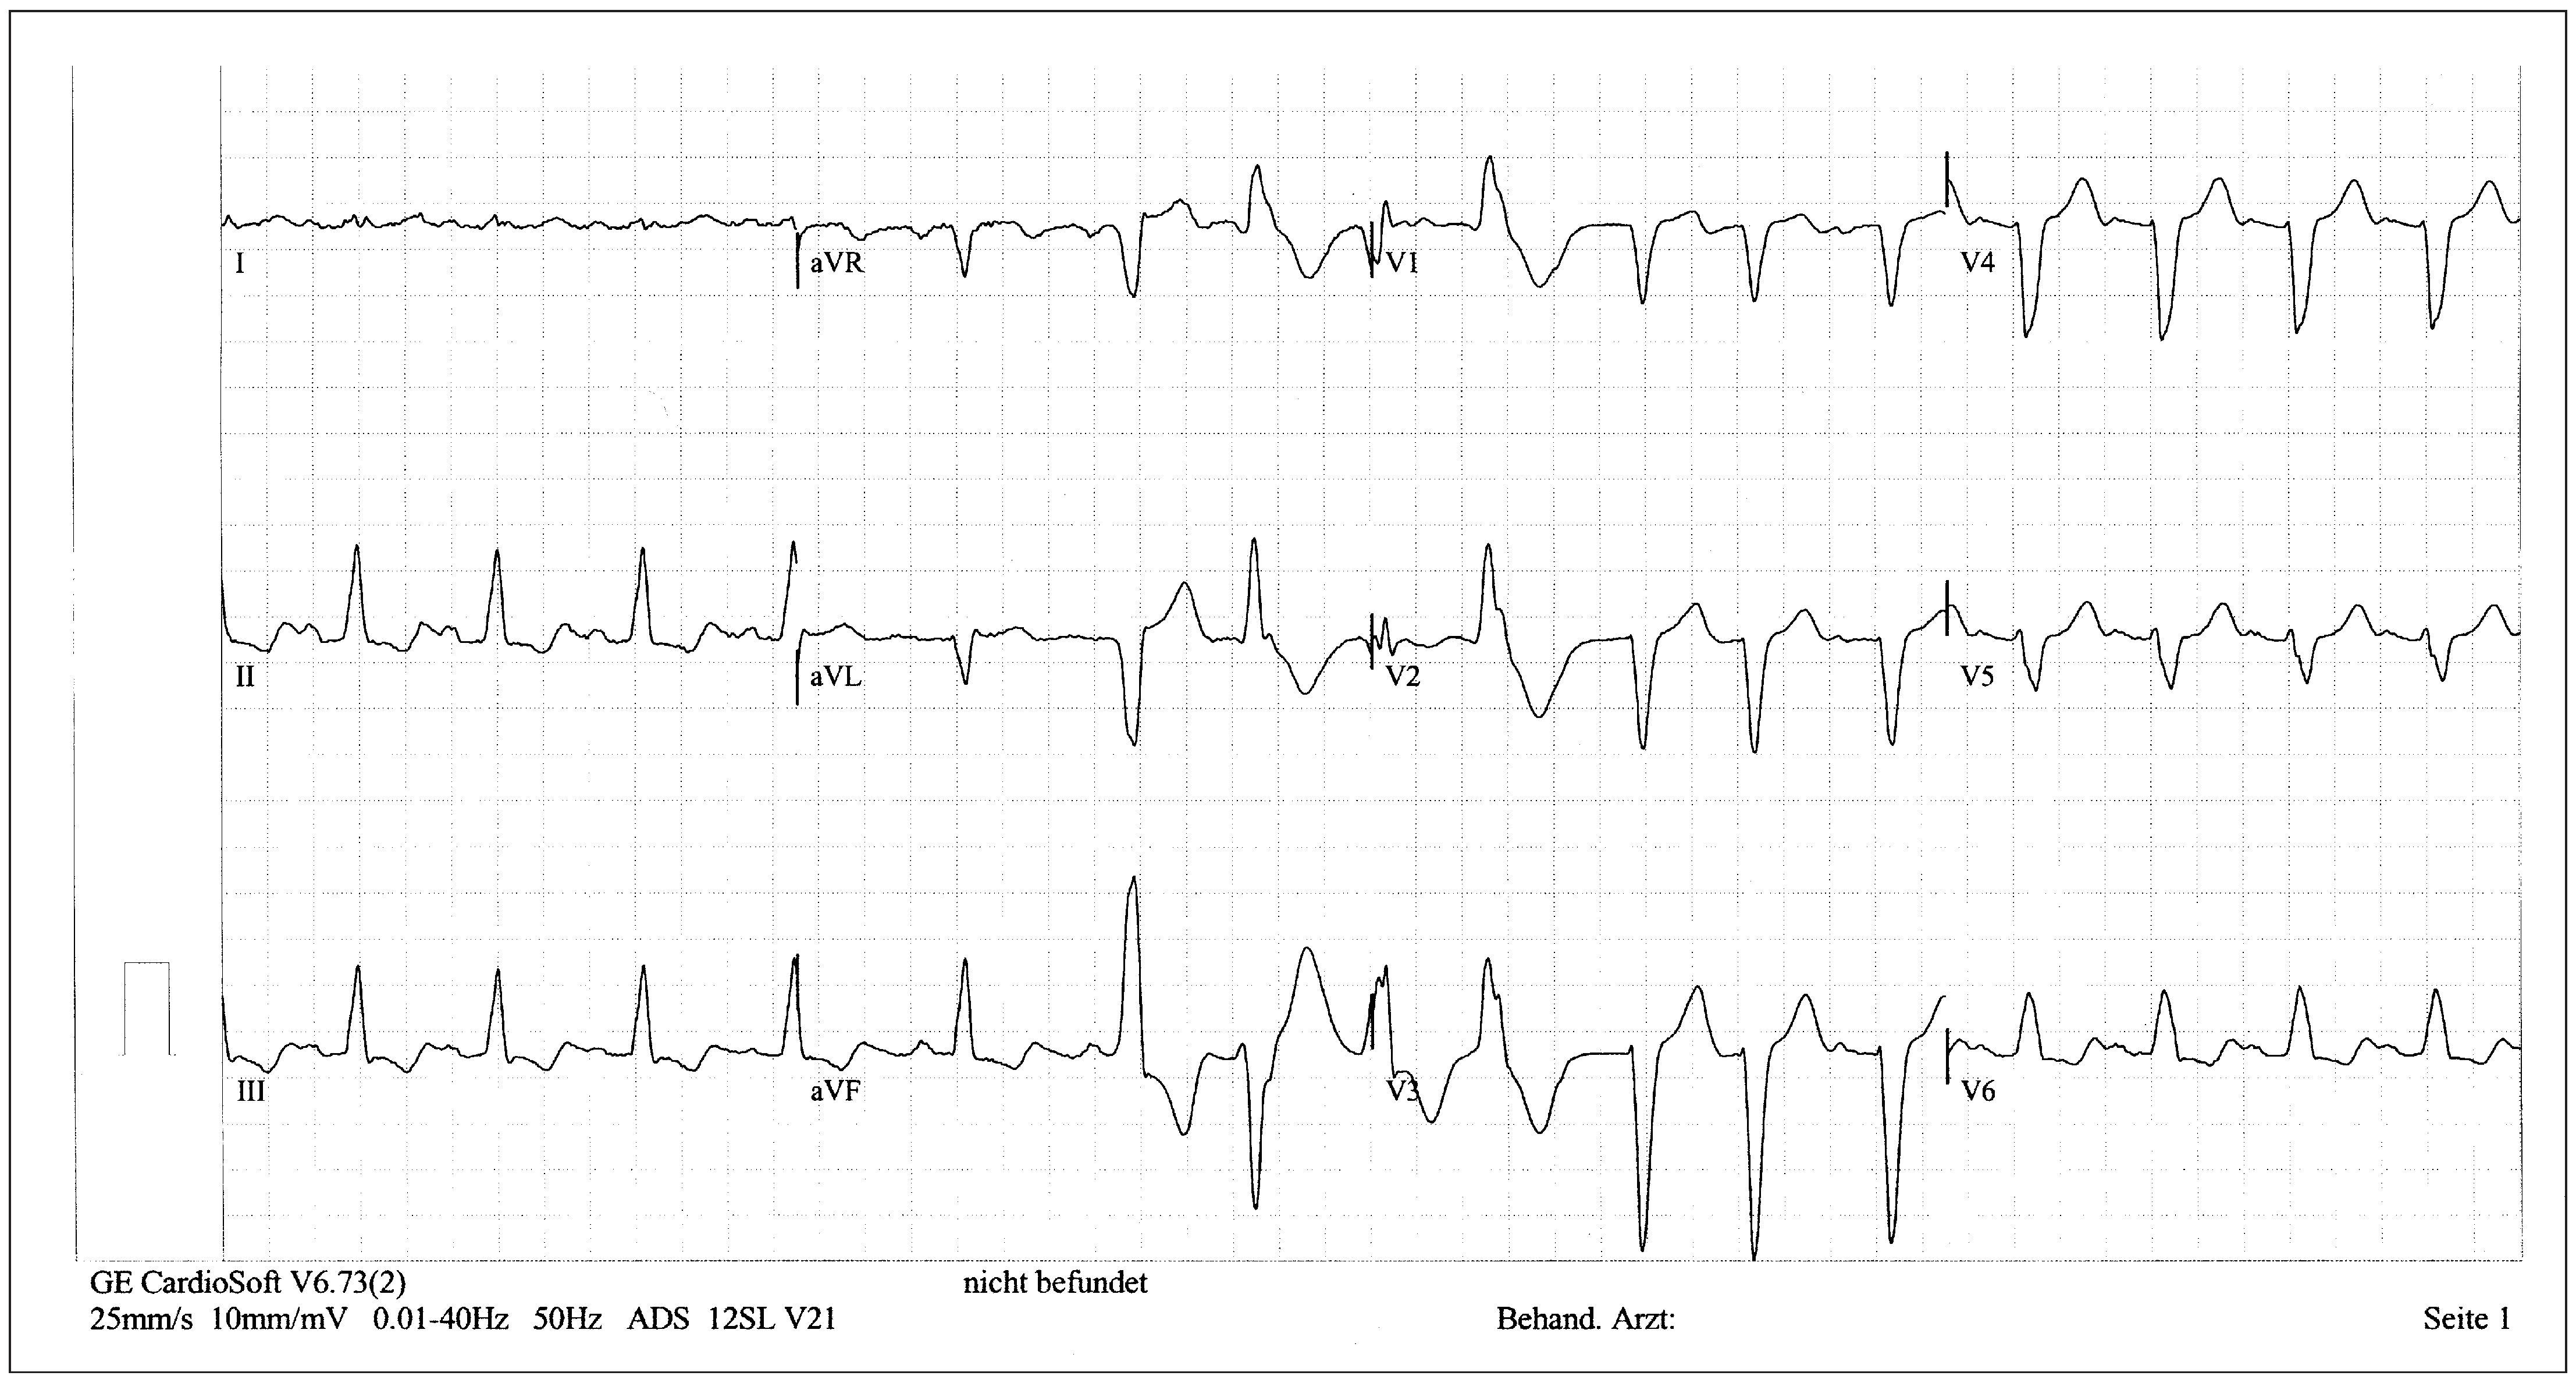

Patient

Six-month follow-up

Sixteen-month follow-up